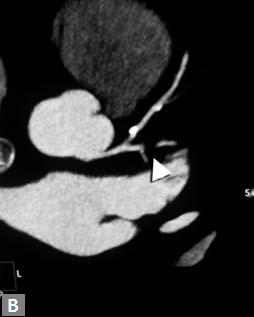

An unusual cause of ischemia is interarterial (so-called

malignant variety) RCA. Demonstration of origin and course

of this vessel is quite easy on CT although the compromise of

lumen is not consistently demonstrated (Figs 7A and B).